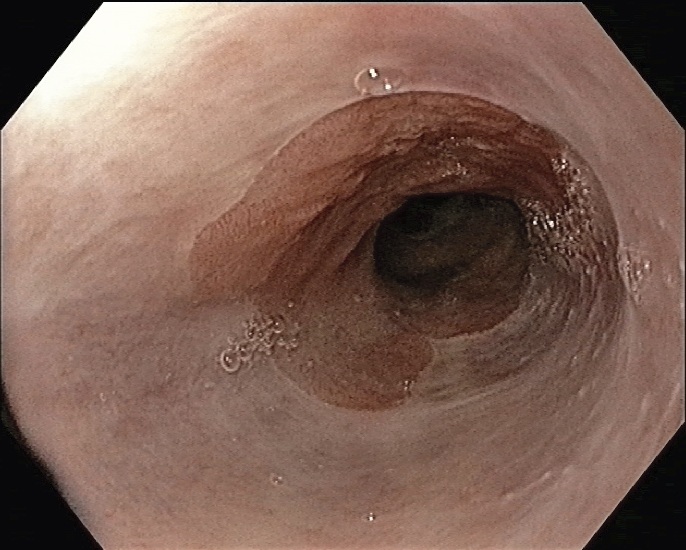

Fallbeskrivning Ovanlig och mycket svår diagnos att ställa